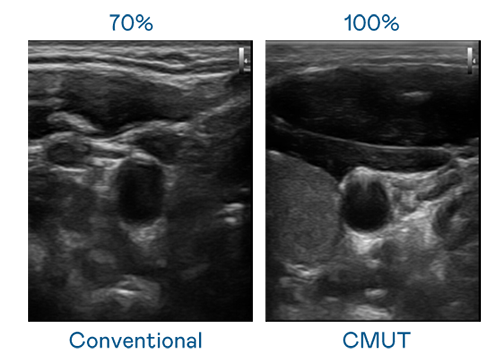

CMUT 技术是一种用电容式微机电元件来产生超音波讯号的技术。与传统 PZT 压电式技术相比,CMUT 频宽增加 30%,更宽频的超音波讯号让影像解析度大幅提升,是实现高影像品质医疗超音波扫描、促进精准医疗发展的关键技术。

超音波影像的解析度高低,首先取决于探头能发出的讯号频宽。豪运国际 CMUT 可提供高清晰的超音波讯号,提供高频宽、高灵敏度、影像纹理细节更高的超音波影像,协助医护人员缩短影像判读时间及利用精准的医疗影像进行诊断。